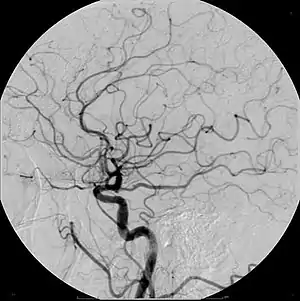

| Cerebral Angiogram obtained using an iodine based contrast medium | |

- Angiogram

Due to positive remodeling the plaque build-up shown on angiogram may appear further downstream on the x-ray where the luminal diameter would look normal even though there is severe narrowing at the real site. Because angiograms require x-rays to be visualized the number of times an individual can have it done over a year is limited by the guidelines for the amount of radiation they can be exposed to in a one-year period.[2]